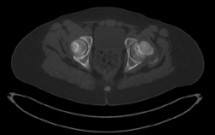

Percorsi clinici

Sclerosi epatoportale

Sparaventi C, Zago A, Di Leo G, Barbi E, Bramuzzo M.

Una nuova condizione epatica, spesso sottodiagnosticata, con una evoluzione variabile, a volte benigna, in altri casi con ipertensione portale. Rara, ma come novità da conoscere e riconoscere.